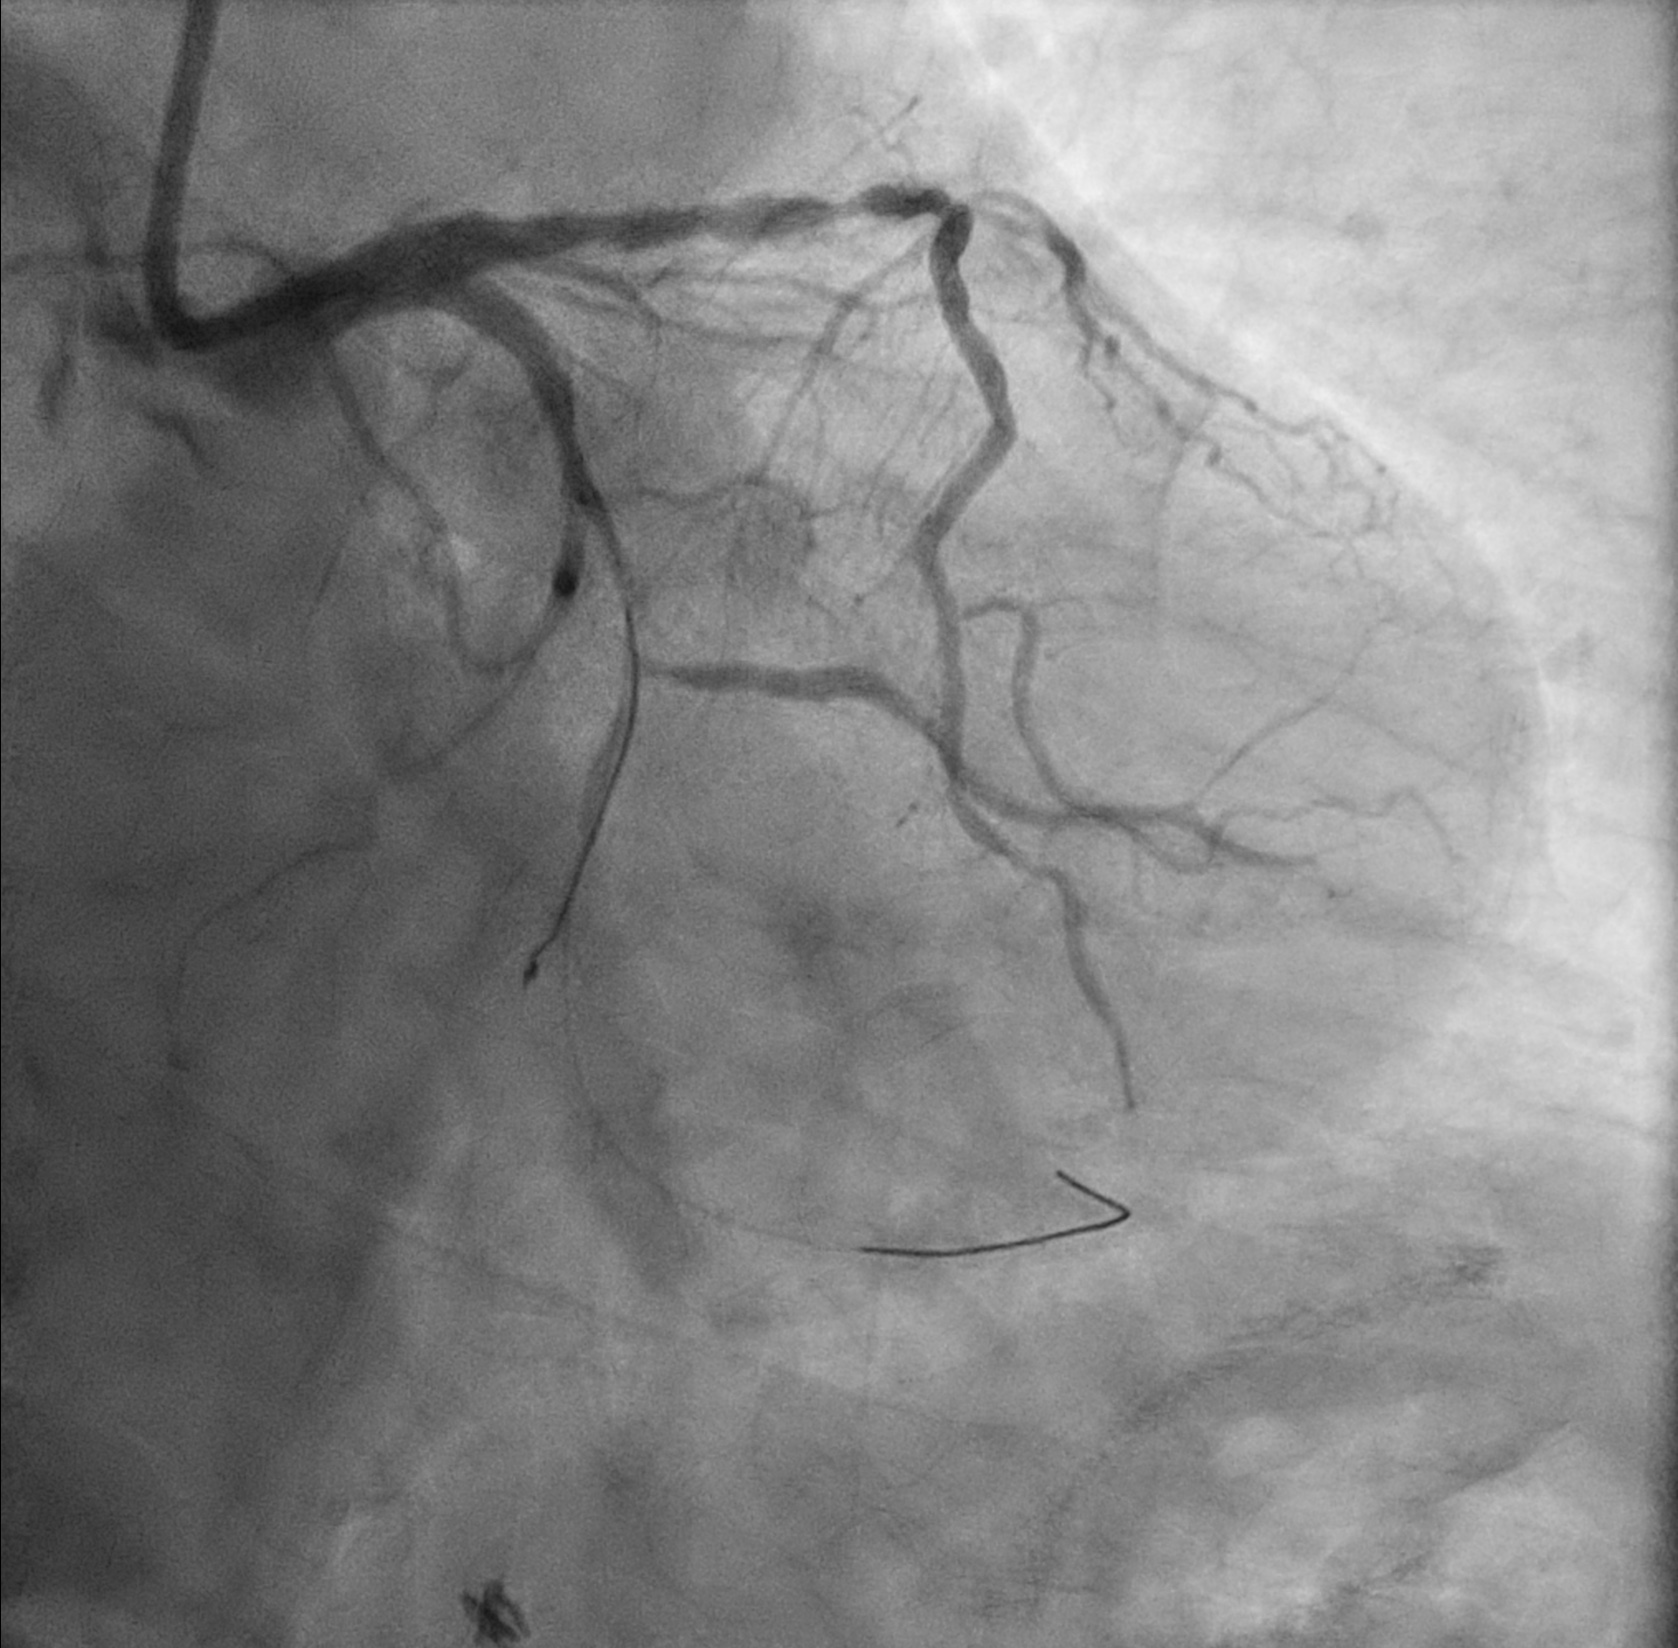

Coronary angiogram- Left main: normal- LAD: p-mLAD diffuse severe stenosis- LCx: mLCx total occlusion, dLCx supplied by septals- RCA: Dominant, pRCA diffuse mild to moderate stenosis, mRCA focal severe stenosis.

Left main was engaged with 7F EBU 3.5. Attempt wiring to mLCx total occlusion by Runthrough NS and Fielder XT-A with Caravel support but failed. mLCx finally wired with Gaia Next 1 and switched to Runthrough NS. Predilation to mLCx with Sapphire 1.0/15 and Ryurei 2.0/15.

After dilation to mLCx, runthrough NS wire knuckled in dLCx and failed to be straightened up. Another Runthrough NS wired to dLCx with Crusade Type R catheter.

On removal of the knuckled runthrough NS, it was stucked in ventricular branch. Cine confirmed coronary guidewire knot was formed.

Final angiogram showed good result.